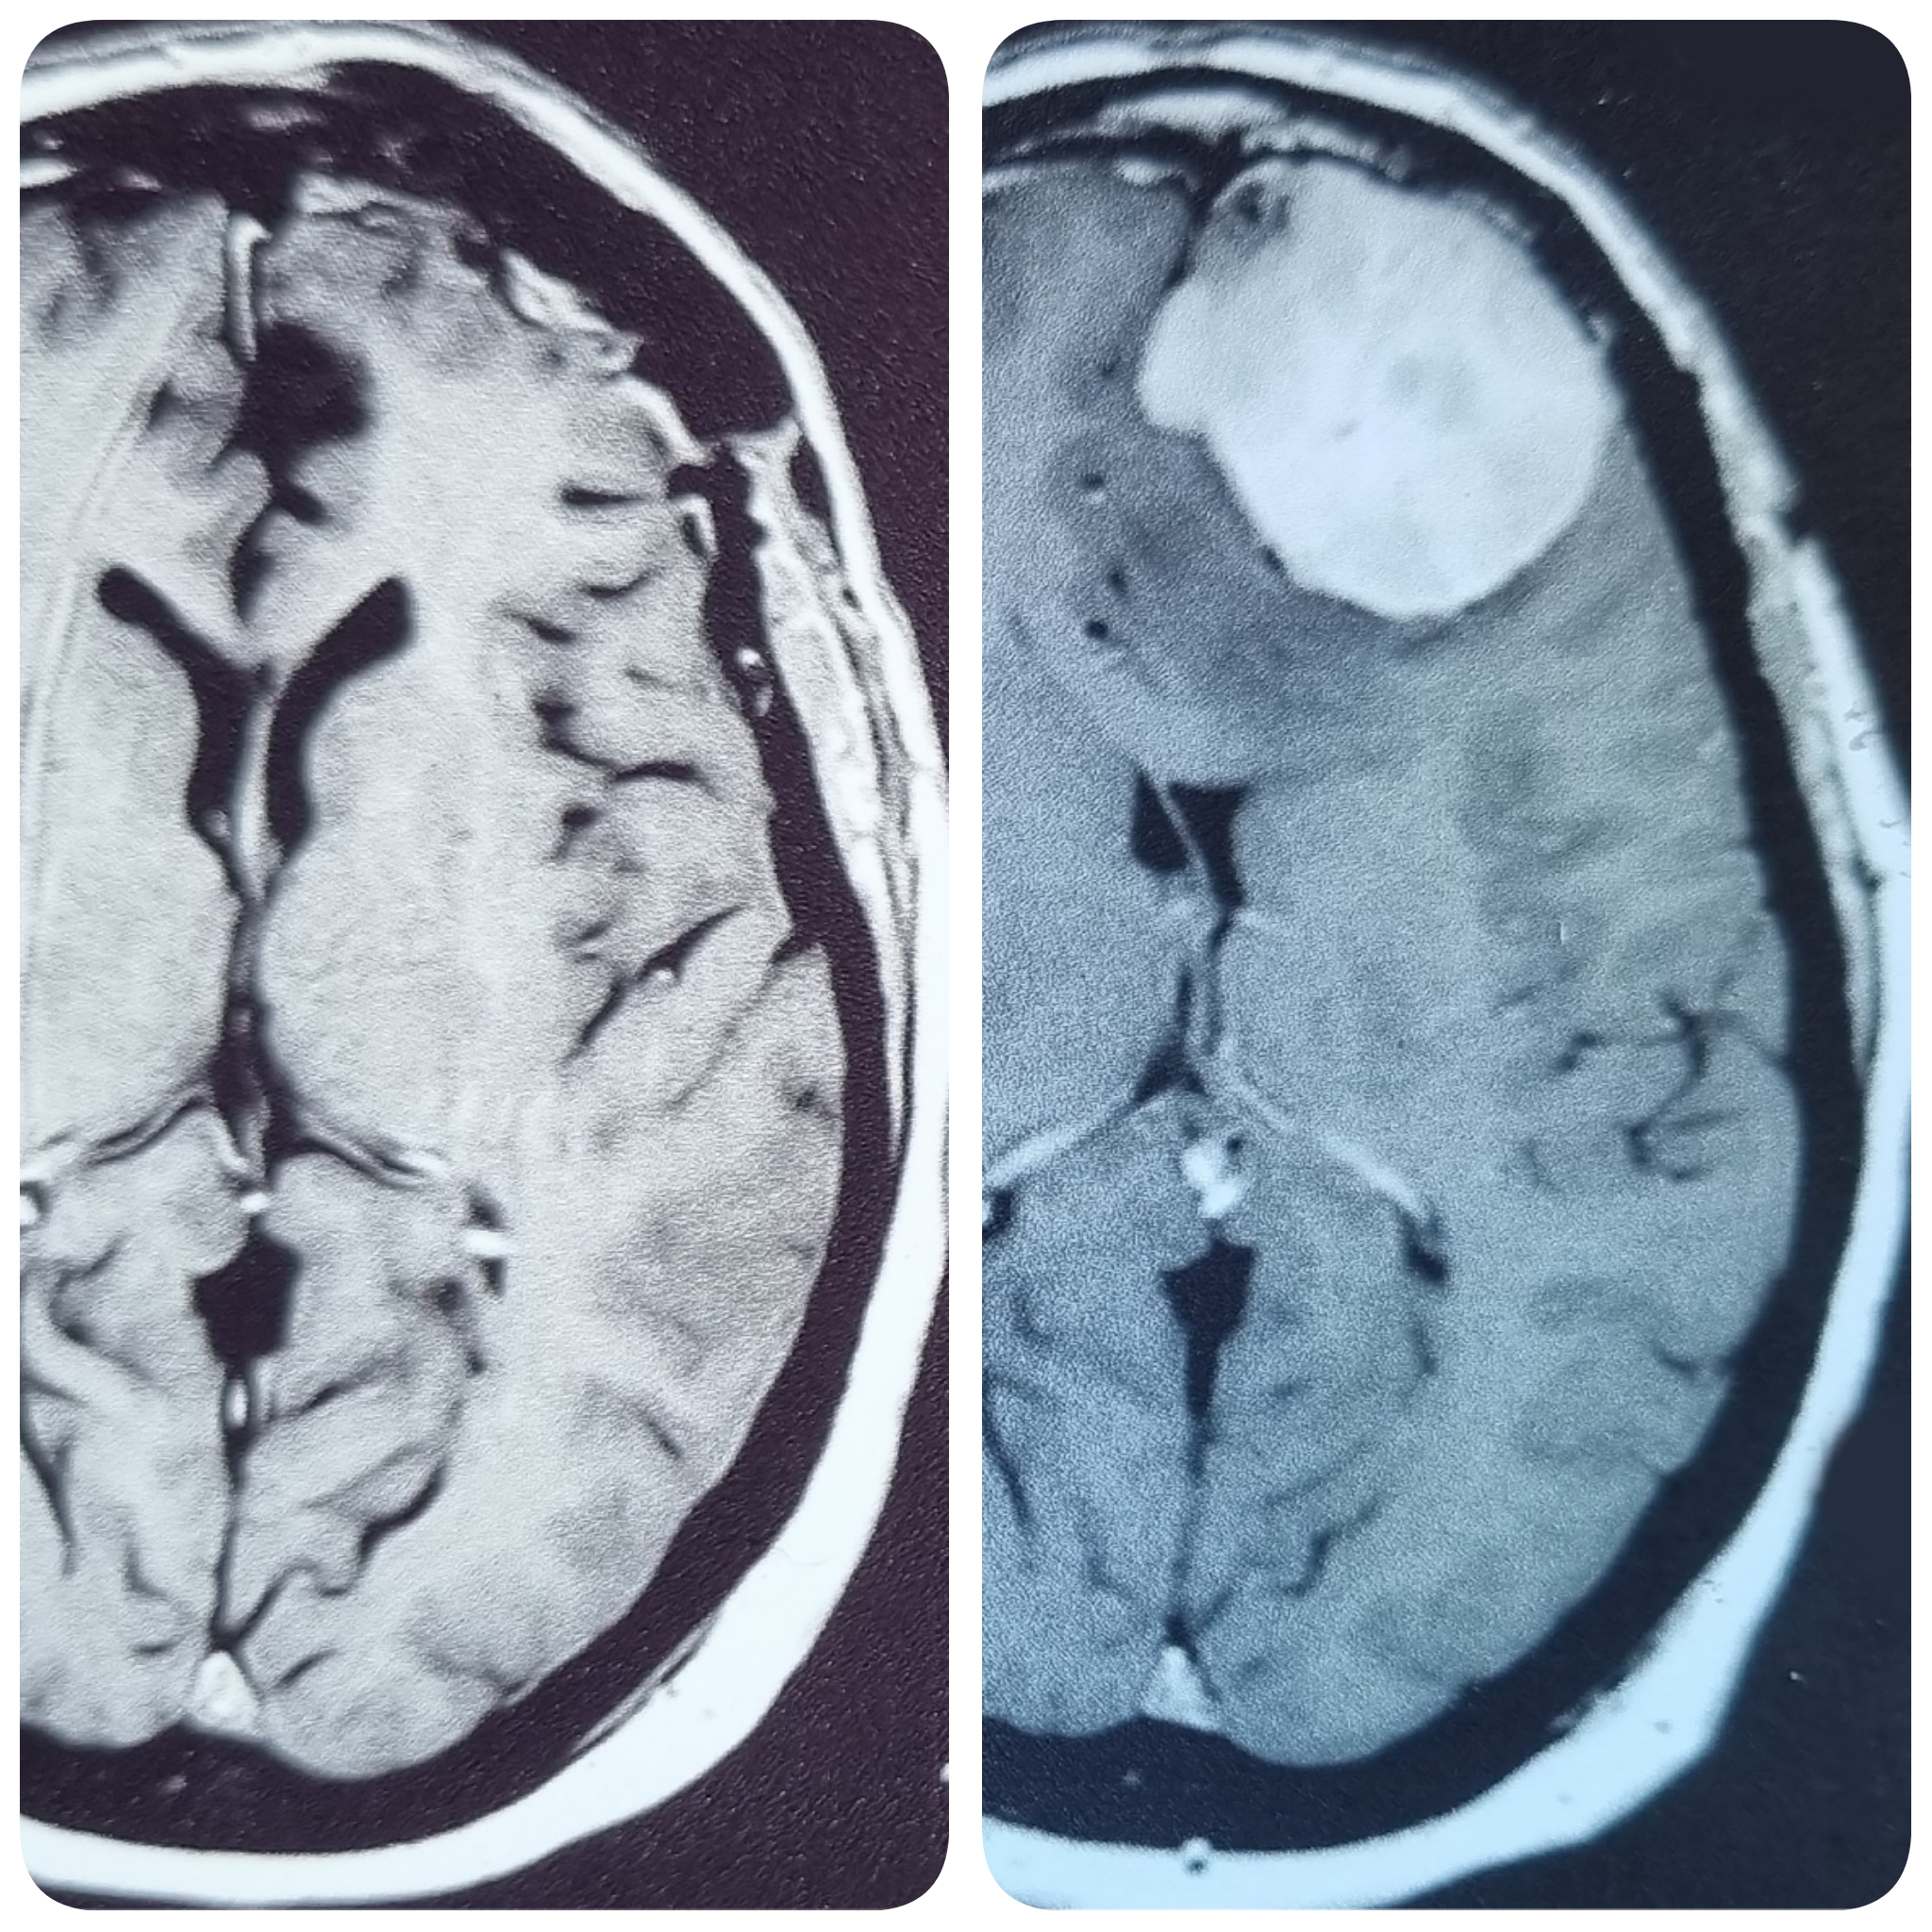

– الرنين المغناطيسي على المخ بالصبغة، والذي يظهر مكان الورم، ويساعد في التخطيط للجراحة.

أمثلة لاستئصال أورام أغشية المخ الحميدة بالجراحة الميكروسكوبية